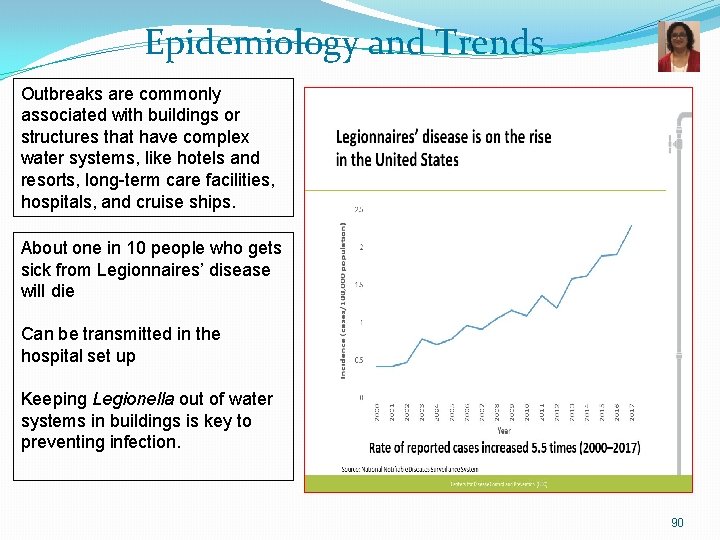

Epidemiology and Trends Outbreaks are commonly associated with buildings or structures that have complex water systems, like hotels and resorts, long-term care facilities, hospitals, and cruise ships. About one in 10 people who gets sick from Legionnaires’ disease will die Can be transmitted in the hospital set up Keeping Legionella out of water systems in buildings is key to preventing infection. 90